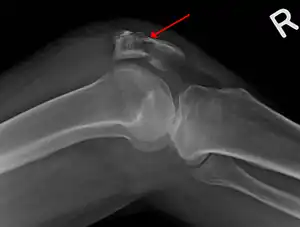

The patella can break in various ways depending on the way it is injured, and into two or more pieces.[1] Types include transverse, with one fracture line and is the most common type,[5] marginal, osteochondral and the rare vertical type, or stellate, where a direct compression force gives rise to a comminuted pattern.[5][7] Patella fractures can be further classified as displaced, where the broken ends of bone do not line up correctly and separate by more than 2mm, or undisplaced and stable where pieces of bone remain in contact with each other.[1][7] If fragments of patella bone stick out from the skin it is known as an open patella fracture, and closed if the overlying skin is intact.[1]

Osteochondral fracture of patella -